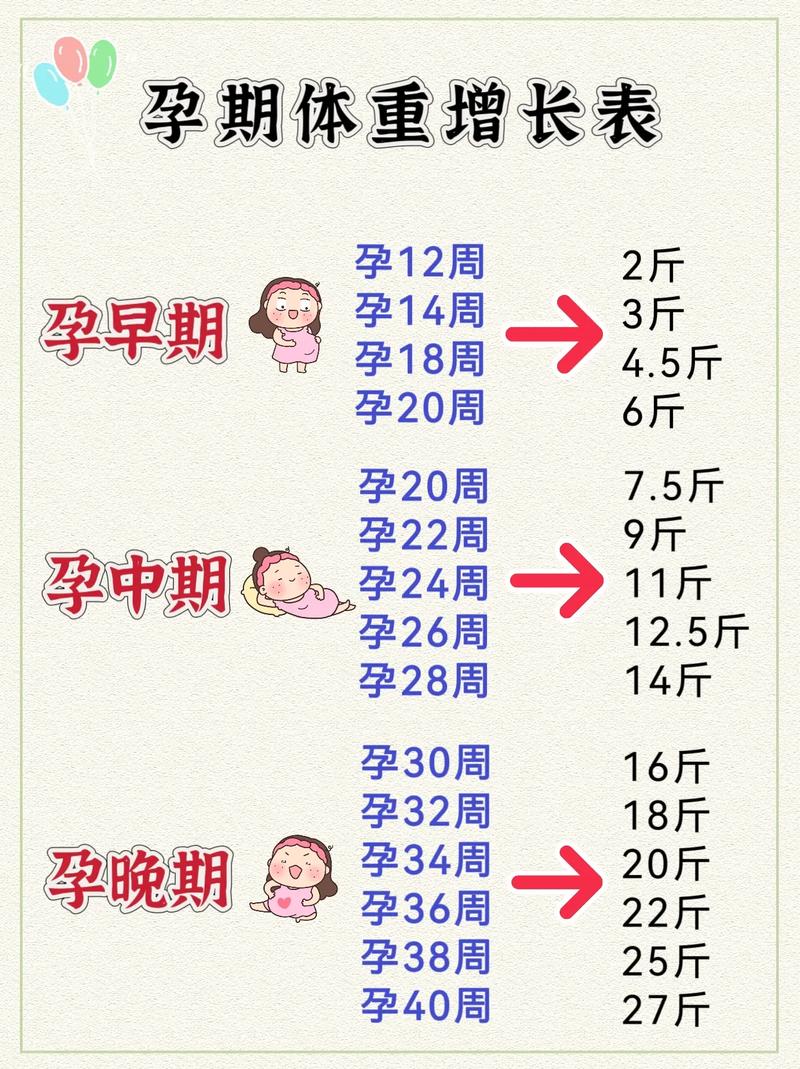

根据中国营养学会《中国居民膳食指南(2025)》和美国妇产科学会(ACOG)的建议,孕期适宜增重范围主要基于孕前BMI来划分:

| 孕前BMI分类 | 孕前BMI范围 (kg/m²) | 推荐总增重范围 (斤) | 平均每周增重(孕中晚期) |

|---|---|---|---|

| 体重过低 | < 18.5 | 22 - 33 斤 | 51 - 0.68 斤 (0.44-0.58 kg) |

| 体重正常 | 5 - 23.9 | 14 - 22 斤 | 37 - 0.58 斤 (0.32-0.50 kg) |

| 超重 | 0 - 27.9 | 7 - 14 斤 | 22 - 0.50 斤 (0.17-0.36 kg) |

| 肥胖 | ≥ 28.0 | 5 - 9 斤 | ≤ 0.22 斤 (≤ 0.17 kg) |